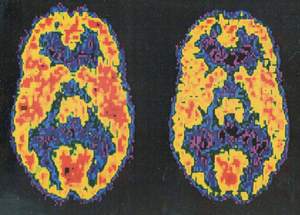

10 năm qua, với các công nghệ hiện đại (xét nghiệm hình ảnh fMRI, PET) các nhà khoa học đạt được tiến bộ đáng kể trong tìm hiểu các cơ chế vật chất của hiện tượng nghiện. Theo đó, hướng các nghiên cứu vào việc: hình dung điều gì đã xảy ra trong não người nghiện? Các chất dẫn truyền thần kinh nào mất quân bình? Ảnh hưởng nào của sự nghiện lên não bộ? Thuốc nào có thể chặn được cơn nghiện?

TS. Nora Volkow, Giám đốc Viện nghiên cứu lạm dụng thuốc (NIDA) nhận xét: Từ thời khởi thủy văn minh, con người đã muốn dùng thử những thứ làm cho mình dễ chịu. Các hệ thống ghi nhớ, các vòng mạch "tưởng thưởng", các phản xạ có điều kiện của chính con người có khuynh hướng vận hành thái quá, dẫn đến nghiện. Xét về khía cạnh này, các thức nghiện giống như một kẻ thù nhằm vào điểm yếu của cơ thể. Nhưng tại sao, trong cuộc chiến ấy, có người không nghiện, có người nghiện rồi cai được, có người không thể cai được, ngã gục, trở thành con nghiện? Dùng kỹ thuật quét não ảnh, TS. Nora Volkow chứng minh có sự tăng hoạt hóa các vùng não kết nối với với các điểm tiếp nhận thức nghiện (miệng, lưỡi, môi). Theo ông sự hoạt hóa các vùng này giống mở cánh cửa dẫn đến "trung tâm lạc thú".

TS. Faulus khi nghiên cứu cai nghiện metamphetamin, nhận xét: có nhóm người bỏ được nghiện, song có nhóm người tái nghiện rất dễ. Nhóm người tái nghiện rất dễ chính là nhóm khó hoàn thành các công việc có kỹ năng nhận thức, khó thích ứng với các qui định mới.. Theo ông, có lẽ họ ít có khả năng dùng các vùng não có chức năng phân tích khi thực hiện các nhiệm vụ, các qui định mới đòi hỏi sự quyết đoán. Dùng kỹ thuật quét não ảnh, TS. Faulus thấy rõ có một sự giảm rõ rệt hoạt tính vùng trán trước của vỏ não là nơi có nhiệm vụ "điều khiển lý trí chống lại thói bốc đồng". Từ đây, có thể hiểu chính thức nghiện làm tổn hại năng lực cho người tái nghiện, khiến chúng ta nghĩ đến có một yếu tố "bẩm tính" nào đó chỉ liên quan đến một số người và gây nên sự tái nghiện. TS. Faulus cũng ngạc nhiên khi chính ông thông qua quét não ảnh đã dự đoán chính xác đến 80% các trường hợp dễ tái nghiện!

Bằng nhiều nhận xét lâm sàng và kỹ thuật quét não ảnh tương tự, các nhà khoa học hình dung: Thoạt tiên, không phải là tất cả mà chỉ có những người do bộ não có những nét riêng (tạm gọi là bản tính) mà nhạy cảm với các thức làm dễ chịu, lạc thú (cụ thể hay trừu tượng - gọi chung thức nghiện) và sa vào bẫy nghiện. Sau đó, những thức nghiện, đến lượt mình, tác động trở lại làm thay đổi các cấu tạo vật chất, các phản xạ não, làm cho người đó ham muốn, khao khát sự dễ chịu , lạc thú (thức nghiện), không thể nào dứt ra được, trở thành người nghiện. Như vậy có mối liên quan, sự tương tác vật chất lên hiện tượng nghiện.